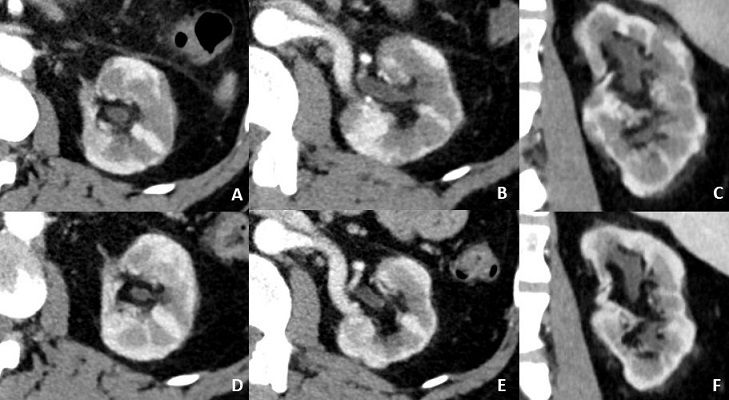

Las lesiones renales en la ER-IgG4 presentan varios patrones de afectación en las pruebas de imagen. La prueba de imagen más utilizada para el estudio de esta enfermedad por su mayor fiabilidad, reproductibilidad y accesibilidad es la tomografía computarizada multidetector (TCMD). Pudiendo presentarse como:

f1

Figura 1. Diferentes formas de presentación de la afectación renal por IgG4. A. Imagen de TCMD en el que se observa un afectación cortical bilateral difusa, con lesiones en cuña hipodensas. B. Lesión redondeada cortical hipodensa simulando una tumoración renal